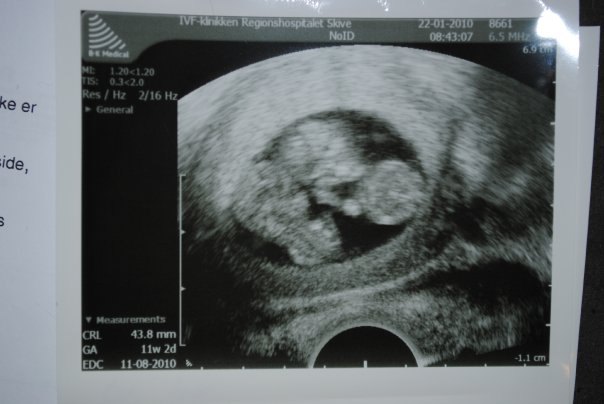

7+0 og man kan næsten ikke se den ene i sin sæk. Der var hjerteblink i begge. Lægen sagde, at han aldrig ville se efter hjerteblink før 7+0, da det bestemt ikke betød, at der ikke var liv, hvis man ikke kunne finde det.

Til højre er jeg 9+0. Der blev de til små "vingumibamser".